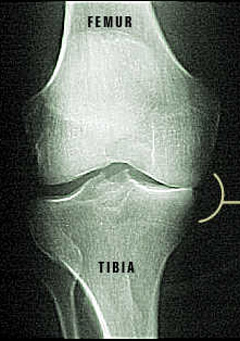

X-ray of Damaged Knee Joint

Notice how the femur is rubbing against the tibia. That is because the cartilage on top of the tibia has been damaged. Since only one side is affected, a partial knee surgery is possible.